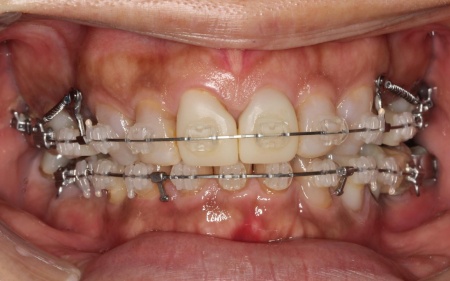

治療前

まずは、口腔内全体の矯正治療から開始します。

上顎は左上の歯が欠損していたため、左右のバランスを整える目的で、右上の歯(第1小臼歯)を抜きました。

その後、ワイヤー矯正とクローズドコイル(バネの装置)を使ったスピード矯正を行い、前歯を後方に移動させます。

下顎は残根も利用しながら、矯正用の小さなネジ「テンポラリーインプラント(インプラントアンカー)」を顎の骨に埋め込んで固定源とする方法も併用し、歯を移動させました。

矯正期間中は定期的に装置の調整を行い、歯の動きや噛み合わせの変化を確認しながら治療を進めています。